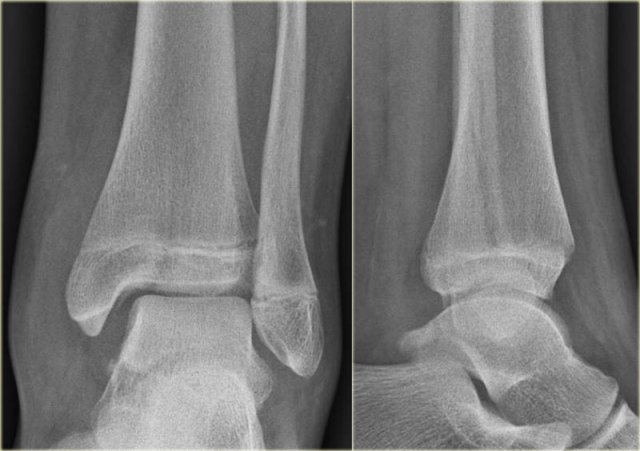

In this case there is a Weber B fracture with avulsion of the medial malleolus.

The bright line on the AP-view indicates a large tertius fracture fragment.

This tertius fracture can also be seen on the lateral view, but in many cases we need all the information of both the lateral and AP-view to diagnose a tertius fracture.